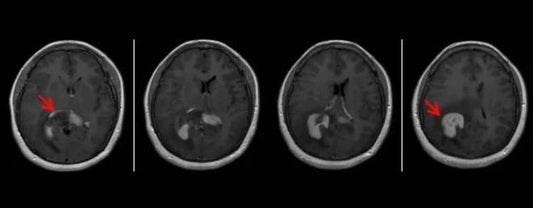

Using $3.0T$ quantitative MRI ($T_{2}$-Mapping & $T_{1}$ Map), the Beijing Radiology Expert Team successfully localized "invisible" lesions by measuring biochemical shifts in the cartilage matrix, establishing a digital baseline for...